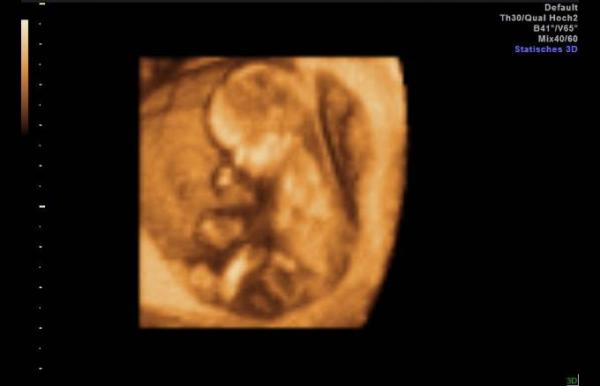

Hallo ihr Lieben, ich bin jetzt auch zurück von meinem Termin und bin total erleichtert. In meinem Urin wurde leider Blut festgestellt, weswegen ich im Wartezimmer umso aufgeregter und unsicherer wurde. Aber beim Ultraschall kam dann die große Erleichterung. Kaum hat man das Kleine im Ultraschall gesehen, hat es einen Sprung gemacht und fleißig gezappelt. Oh man war ich erleichtert. Eine Ursache für das Blut wurde zwar nicht gefunden, aber solange es dem Baby gut geht, muss ich mir keine Sorgen machen. Jetzt wird die Zeit für mein Gefühl hoffentlich entspannter, da ich morgen auch in die 13. Woche rutsche und so eine schwierige Phase schon geschafft ist. Meinen Mutterpass habe ich heute auch endlich bekommen, also toll toll toll. Für alle anderen, die heute auch einen erfolgreichen Termin hatten, freue ich mich auch riesig und gratuliere recht herzlich und allen anderen drücke ich die Daumen für ihre nächsten Termine. LG

Ach, ein schönes Bild habe ich auch noch.

Das ist wirklich ein tolles Bild! Schön das alles in Ordnung :)

Das ist wirklich ein wunderschönes Bild. Herzlichen Glückwunsch und alles Gute für Euch

Das ist ja putzig! Sieht schon aus wie ein richtiges Baby! :) Glückwunsch zum Überstehen der ersten Hürde!

Wunderschönes Bild, direkt in 3D hätte ich auch gerne gehabt hihi toll das alles super ist. Das beruhigt mich aktuell auch sehr. Blut im Urin ist nicht so toll aber kann bei einem Infekt glaube ich vorkommen. Alles Liebe weiterhin

Oh wow, ist das ein tolles Bild!! Ich freue mich für euch, dass alles so ist, wie es sein soll!! Und endlich 13. SSW! Ich bin auch froh, wenn die erste 12 Wochen nächste Woche rum sind Auch für euch alles Liebe